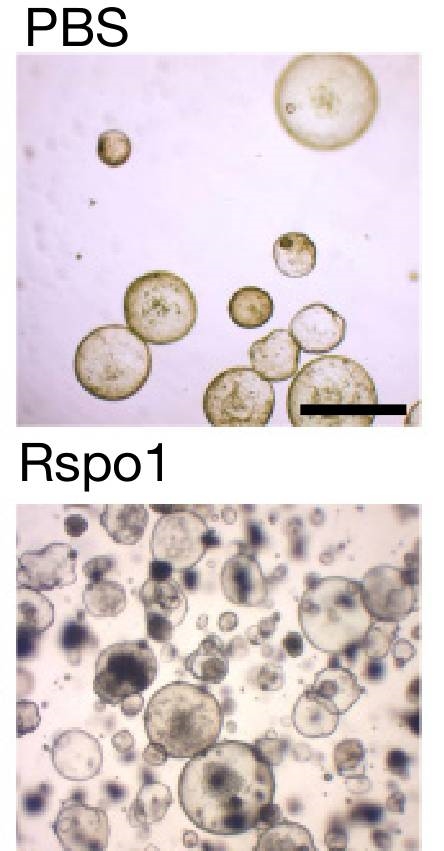

ňÉÂ�´╝î�´╝î�´╝î�´╝îMeyerňŹÜňúźŔ┐śňĆĹŠśÄ�´╝î�´╝î�´╝î�´╝îňŻôň╣ŻÚŚĘŔ×║ŠŁćŔĆîńżÁňůąŠŚÂ�´╝î�´╝î�´╝î�´╝îŔââš▓śŔćťńŞőŠľ╣šÜäÚŚ┤Ŕ┤ĘŠłÉš║Ąš╗┤š╗ćŔâ×ń╝ÜŠŞŚÚÇĆńŞÇšžŹňÉŹńŞ║R-ŔäŐÚźôňŹÁšÖŻ´╝łRspo´╝ëšÜäšëęŔ┤Ę�´╝î�´╝î�´╝î�´╝îńŻťšöĘń║ÄŔââš▓śŔćťńŞőŠľ╣ň╣▓š╗ćŔâ׊▒á�´╝î�´╝î�´╝î�´╝îŠ┐ÇŠ┤╗ň╣▓š╗ćŔâךÜäWNTÚÇÜŔĚ»Ŕ░âšÉćň╣▓š╗ćŔâךÜäňó׊«ľń╗ąň║öň»╣ň╣ŻÚŚĘŔ×║ŠŁćŔĆîšćĆŠčôŃÇé�ŃÇéŃÇé�ŃÇé�ŃÇé

ňĆ»Šś»�´╝î�´╝î�´╝î�´╝îMeyerňŹÜňúźňĆĹŠśÄ�´╝î�´╝î�´╝î�´╝îŔ┐ÖńŞĄšžŹš╗ćŔâ×ň»╣WNTÚÇÜŔĚ»šÜäňĆŹň║öŠś»ňĚ«ňłźšÜäŃÇé�ŃÇéŃÇé�ŃÇé�ŃÇ銺úňŞŞRspońŻťšöĘń║ÄňłćŔžúŠ░┤ň╣│ńŻÄ�´╝î�´╝î�´╝î�´╝îňó׊«ľŔżâň┐źšÜäň╣▓š╗ćŔâ×ňťĘňÉÄ�´╝î�´╝î�´╝î�´╝îń╝ÜńŻ┐ň╣▓š╗ćŔâךÜäňó׊«ľÚÇčšÄ犜żŔĹŚňŐáÚÇč�´╝î�´╝î�´╝î�´╝îň»╝Ŕç┤ňůÂňĄ¬Ŕ┐çňó׊«ľŃÇé�ŃÇéŃÇé�ŃÇé�ŃÇéŔÇîRspońŻťšöĘń║Äňó׊«ľŔżâŠůóšÜäš╗ćŔâ×ňÉÄ�´╝î�´╝î�´╝î�´╝îń╝ÜŠśżŔĹŚŠŐĹňłÂňůÂňó׊«ľŃÇé�ŃÇéŃÇé�ŃÇé�ŃÇé

Rspoń╝ÜŠśżŔĹŚňó×ň╝║ŠĽĆŠäčň╣▓š╗ćŔâךÜäŠëęňó×ÚÇčšÄç´╝łňŹĽš╗ćŔâ×ńŻťŔé▓24ň░ĆŠŚÂ´╝ë

ŠşúňŽéSigalňŹÜňúźŠëÇŔ»┤�´╝î�´╝î�´╝î�´╝î“šö▒ń║Äň╣ŻÚŚĘŔ×║ŠŁćŔĆîň╝ĽŔÁĚšćĆŠčôŠť║ńŻôŠŚáŠ│ĽŔ笊łĹŠ▓╗Šäł�´╝î�´╝î�´╝î�´╝îňŤáŠşĄ�´╝î�´╝î�´╝î�´╝îŔőąńŞŹŠ▓╗šľŚ�´╝î�´╝î�´╝î�´╝îň╣ŻÚŚĘŔ×║ŠŁćŔĆîňĆ»Ŕ⯊üĺń╣ůńŞÇŔ┐×ňł║Š┐ÇÚŚ┤Ŕ┤ĘŠłÉš║Ąš╗┤š╗ćŔâ×ŠŞŚÚÇĆRspoŠŁąňł║Š┐Çň╣▓š╗ćŔâךá┤šóÄ�´╝î�´╝î�´╝î�´╝îŔ┐Öń╣čŔ«ŞŔÂ│ń╗ąŔ»áÚçŐńŞ║ń╗Çń╣łň╣ŻÚŚĘŔ×║ŠŁćŔĆîšćĆŠčôń╝ÜŠśżŔĹŚňó׊Ě╗ŔââšÖîňŹ▒ň«│´╝ł10´╝ëŃÇé�ŃÇéŃÇé�ŃÇé�ŃÇé”

ŠÇ╗šÜ䊣ąŔ»┤�´╝î�´╝î�´╝î�´╝îMeyerňŹÜňúźšÜäšáöšęÂň▒ĽšÄ░ń║ćŠůóŠÇžš╗ćŔĆîšćĆŠčôŠś»ŠÇÄŠáĚŠ╗őŠë░š╗äš╗çšÜäňŐ芼łšÜä�´╝î�´╝î�´╝î�´╝îň╣ŠĆÉńżŤń║ćňů│ń║Äň╣ŻÚŚĘŔ×║ŠŁćŔĆîŠÇÄŠáĚňó׊Ě╗ŔââšÖîňŹ▒ň«│šÜäÚŽľńެňÉŹŔ┤Áš║┐š┤óŃÇé�ŃÇéŃÇé�ŃÇé�ŃÇéŔÇĹňŤŻšöčÚŻ┐ňč║ŠĽ░ňĄž�´╝î�´╝î�´╝î�´╝îň╣ŻÚŚĘŔ×║ŠŁćŔĆîšÜäšćĆŠčôšÄçÚźś�´╝î�´╝î�´╝î�´╝îŔ┐Öń╣芜»ŠłĹňŤŻŔââšÖîňĆĹšŚůń║║ŠĽ░ń╗ąňĆŐŠ«ĺňĹŻń║║ŠĽ░ń║Ĺń║Ĺń╣őÚźśšÜäňĆ»Ŕ⯚╝śŠĽůňÄčšö▒ŃÇé�ŃÇéŃÇé�ŃÇé�ŃÇéŔÇĄň돚ÜäšáöšęŠë╣Š│Ę�´╝î�´╝î�´╝î�´╝îńŞżŔíîň╣ŻÚŚĘŔ×║ŠŁćŔĆîŠá╣Š▓╗Š▓╗šľŚňĆ»ń╗ąÚĽîŠ▒░65%šÜäŔââšÖîňŹ▒ň«│´╝ł11´╝ëŃÇé�ŃÇéŃÇé�ŃÇé�ŃÇéňŤáŠşĄ�´╝î�´╝î�´╝î�´╝îńŞ║ń║ćÚĽîŠ▒░ŔââšÖîšÜäšłćňĆĹ�´╝î�´╝î�´╝î�´╝îšćĆŠčôŔÇůšůžŠŚžň║öŔ»ąň░ŻŠŚęŠÄąňĆŚň╣ŻÚŚĘŔ×║ŠŁćŔĆîŠá╣ÚÖĄŠ▓╗šľŚŃÇé�ŃÇéŃÇé�ŃÇé�ŃÇé